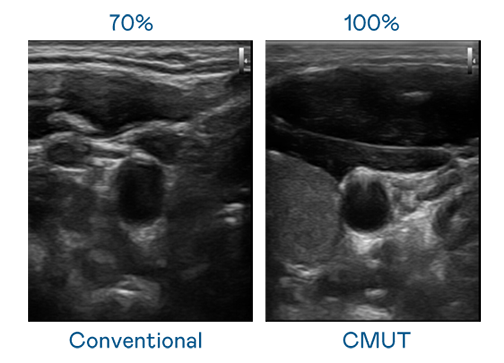

CMUT 技术是一种用电容式微机电元件来产生超音波讯号的技术。与传统 PZT 压电式技术相比,CMUT 频宽增加 30%,更宽频的超音波讯号让影像解析度大幅提升,是实现高影像品质医疗超音波扫描、促进精准医疗发展的关键技术。

大频宽带来超清晰影像

超音波影像的解析度高低,首先取决于探头能发出的讯号频宽。金年会官方网站入口 CMUT 可提供高清晰的超音波讯号,提供高频宽、高灵敏度、影像纹理细节更高的超音波影像,协助医护人员缩短影像判读时间及利用精准的医疗影像进行诊断。